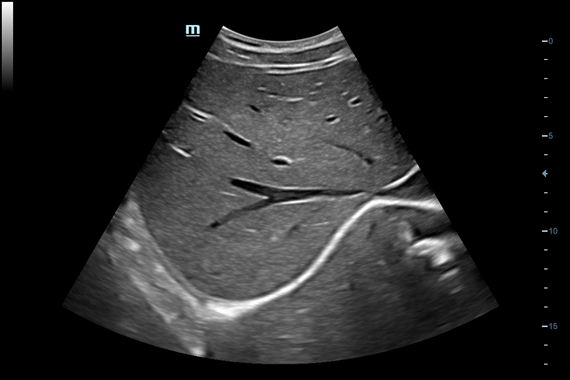

Система ультразвукового исследования Mindray DC-60 EXP X-INSIGHT является новейшей разработкой для проведения комплексных обследований на высшем уровне. Она обеспечивает решение самых сложных задач в таких областях, как кардиология, акушерство и гинекология, сосудистые заболевания, педиатрия и многие другие.

DC-60 EXP X-INSIGHT - это современный стационарный УЗИ-аппарат с функцией сенсорного управления и очищенной гармонической визуализацией, обеспечивающей лучшее контрастное разрешение и технологию 4D-визуализации. Он оснащен 21,5-дюймовым монитором, который может поворачиваться на 180 градусов, что удовлетворяет потребности врачей в качественной ультразвуковой диагностике.

• Vascular package - предустановленные параметры, аннотации, маркеры, программы измерений для ангиологии, включая транскраниальные исследования